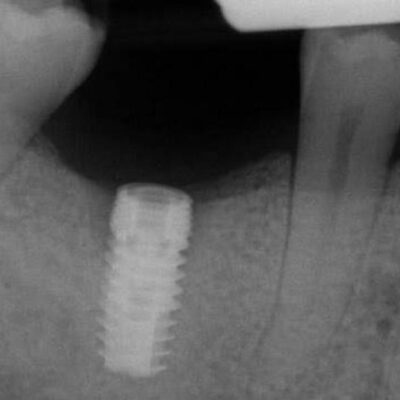

The patient presented on referral for retrieval of a fractured abutment and abutment screw from a BlueSkyBio 4.3 Max implant in the #30 site. The implant was placed on 02.12.2019 and restored on 06.24.2020. The fracture occurred in March of 2023. The case was restored with a Sirona TiBase abutment and a Cerec Emax crown. When the patient recently presented with the fractured abutment the referring Dr. could not retrieve either the retained abutment fragment or screw, so the patient was referred to our practice. When a case presents with both a fractured abutment and abutment screw it is generally easier to recover the abutment fragment first and then the screw as there is better access for the screw retrieval. With an open through bore that is the case here, so the abutment fragment was retrieved with a modified “easy-out” type screw extractor. Next, the screw fragment was evaluated and found to be mobile and residing slightly above the first implant thread, so it was a Type I case in my screw recovery algorithm. Under microscope guidance, the screw fragment was delivered with just an endodontic explorer and a modified endodontic spoon. The implant was cleaned and examined to be free of visual defects at the 25x level of visual inspection. The patient was dismissed to return to the referring doctor for restoration of the case. Prior to leaving a discussion was entertained regarding abutment types and the suggestion was made to consider avoiding another TiBase designed abutment and instead opting for a Custom Base abutment which will have a more robust titanium cross section above the implant top.

So why did this case fail in such a short period of time? I can account for a couple of reasons which may have acted together. First, this implant connection is a clone of the Nobel Conical 3.5 NP connection. Nobel only uses it in their 3.5 implant. They have a larger connection in their 4.3 and 5.0 conical implants, the RP connection. BlueSkyBio in the Max NP line ports the same NP connection in all diameters of the Max NP line. Therefore, this 4.3mm implant has a connection originally designed for a 3.5mm implant. Routinely, I measure the area of the abutment fracture zone to better understand the mechanism of failure and the dimensions are added to a spreadsheet for comparison. This fracture area measured 4.2 sq.mm. To put that into perspective, the Ankylos two piece abutment has an area of 3.97sq.mm at the same critical area at the implant top. The Ankylos solid abutment has 4.95sq.mm. as there is no though bore. To date, I have recovered over 230 fractured Ankylos abutments and I have recovered about 20 two piece abutments to 1 solid. I also have recovered many Straumann RC fractured abutments which have 6.11 sq.mm in this same fracture zone. As I would expect, there have been significantly less Straumann RC abutment fractures than Ankylos but sadly enough there are more than you might think. Secondly, in a TiBase abutment, as in this Sirona TiBase, the cylinder wall is thin and is especially vulnerable to fracture at the junction of the base shoulder and the vertical cylinder. However, in this case the fracture extended well below the implant top into the conical connection. It seems reasonable to hypothesize the fracture started to propagate in the thinnest cross section and extended from there. I’m not yet clear if the thinnest area is at the cylinder wall or deeper into the conical area but logically it seems like the fracture started first at the cylinder base junction and traversed lower through the conical area. Hopefully that is the case, as changing to a Custom Base abutment will eliminate the thin wall at the TiBase cylinder and shoulder but will do nothing to help the conical wall thickness as that is a limitation of the 3.5mm connection design and one of the draw backs from porting a smaller connection into a larger diameter implant.